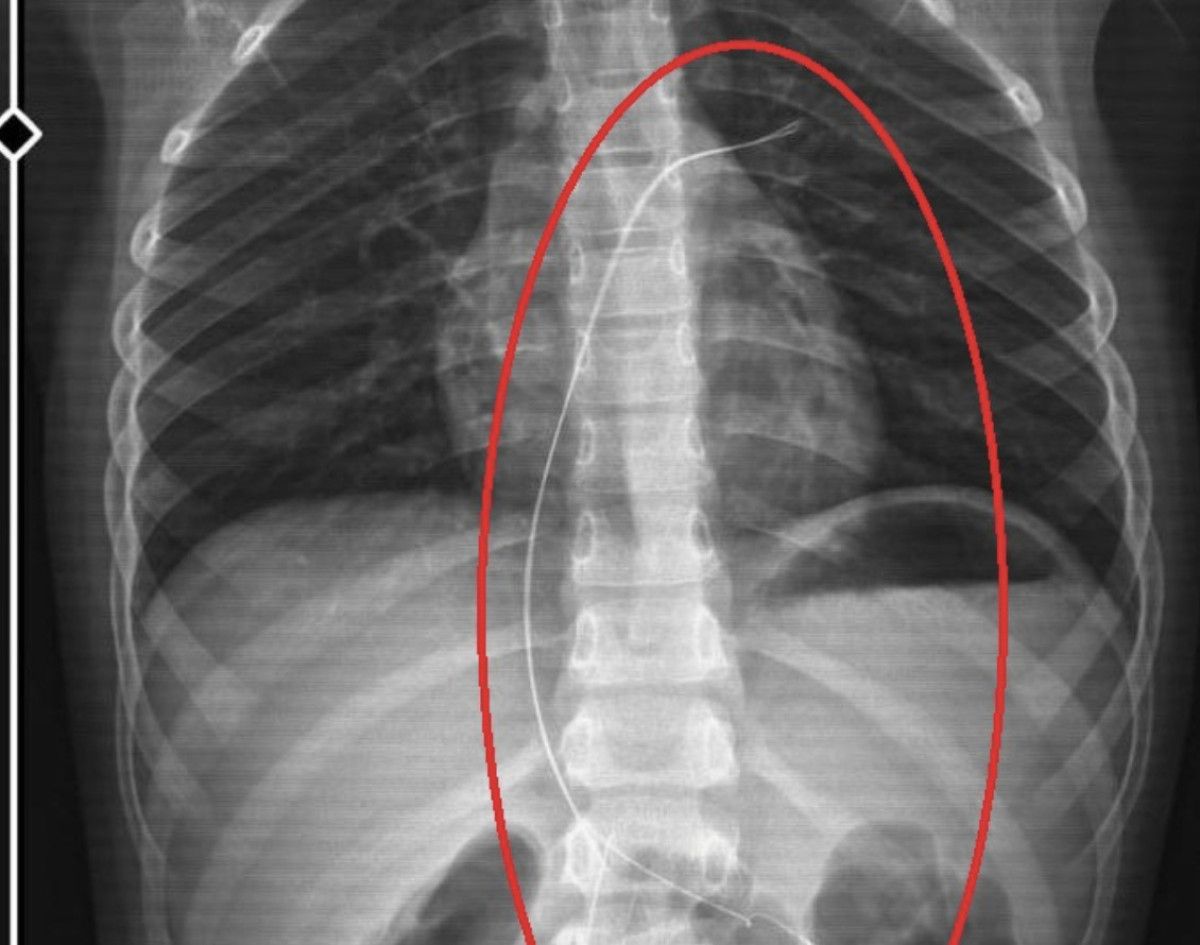

Burada çekilen röntgen ve MR’da Aram’ın vücudunda kateter unutulduğu görüldü.

Müvekkilim Aram Devran Ötün, 2022 Eylül ayında Dicle Üniversitesi Hastanesi’nde Stevens- Johnson hastalığı nedeniyle tedavi gördü. Tedavi sırasında kendisine kateter takıldı. 18 santimetre uzunluğundadır.

Bunu takarken büyük bir ihmalkarlık yapılarak vücudunda unutuldu. Mayıs ayında müvekkilim çok öksürdüğü için Şırnak Devlet Hastanesi’ne kaldırıldı. Burada yapılan tetkiklerde kateterin unutulduğu tespit edildi.

Bu kateterin vücutta yol aldığı tespit edildi. İlk giriş yeri ve çıkarıldığı yer arasında çok fark var ve kalp kapakçığı ile ciğerlerine zarar verdiği tespit edildi.

Röntgeni ve MR’ı çekildi. Tuhaf bir şey olduğunu anladık. Doktor röntgeni gösterdi. Tel kalmıştı. Çok kötü bir şekilde. Acil doktoru film çektikten sonra bize bir tel parçasını gösterdi. Bizi bekletmeden Diyarbakır’a sevkimizi verdiler. Diyarbakır Gazi Yaşargil Eğitim ve Araştırma Hastanesi Kadın Doğum ve Çocuk Ek Binası’na gittik.